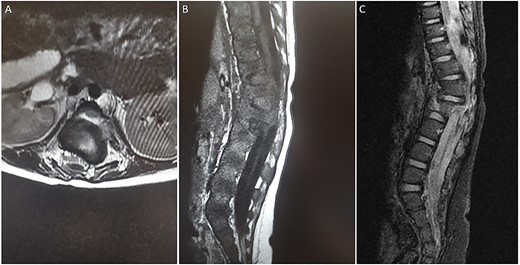

A spine radiograph and CT scan (Figs 1 and 2) revealed a three-column fracture of T12-L1 and an L2 body fracture. A multiplanar and multisequential MR images (Fig. 3) of the whole spine were performed utilizing trauma protocol. The images demonstrated narrowing of the spinal canal at the level of thoracolumbar junction secondary to multilevel fractures along with myelomalacia changes involving the lower thoracic cord and conus medullaris. Additionally, the images showed an evidence of kyphosis measuring 47° at the fracture site.

(A) axial T2-weighted MRI. (B) Sagittal T1-weighted MRI (C) Sagittal STIR MRI. (A-C) There are multiple fractures involving the lower thoracic and upper lumbar spine with involvement of the posterior columns and narrowing of the spinal canal. There is a large extramedullary lesion likely representing a small subdural hematoma.